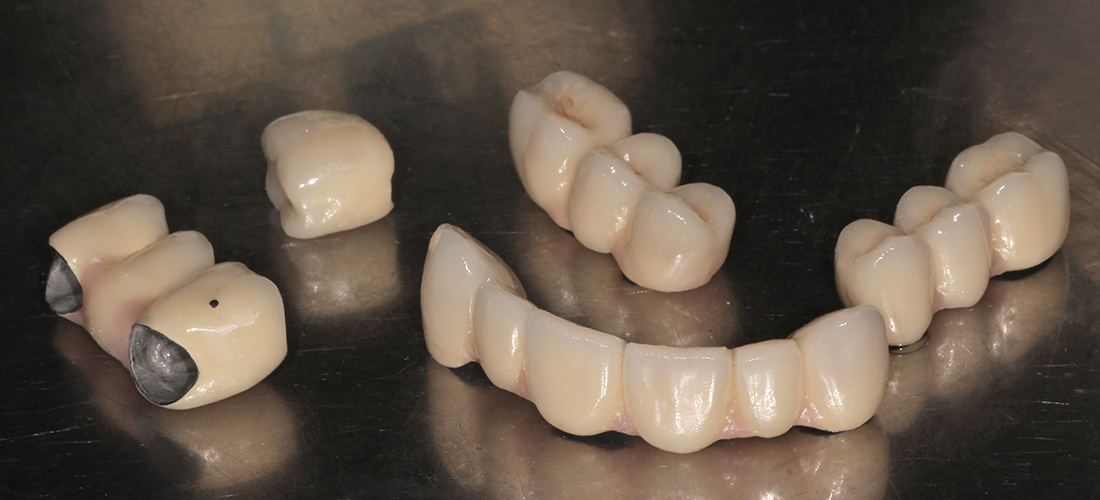

Окончательное протезирование было выполнено тремя металлокерамическими мостовидными конструкциями на верхней челюсти, мостовидным протезом внизу справа и отдельной коронкой на импланте в области шестого зуба нижней челюсти слева. Фиксация коронок проводилась на индивидуальные циркониевые абатмены одноэтапно.